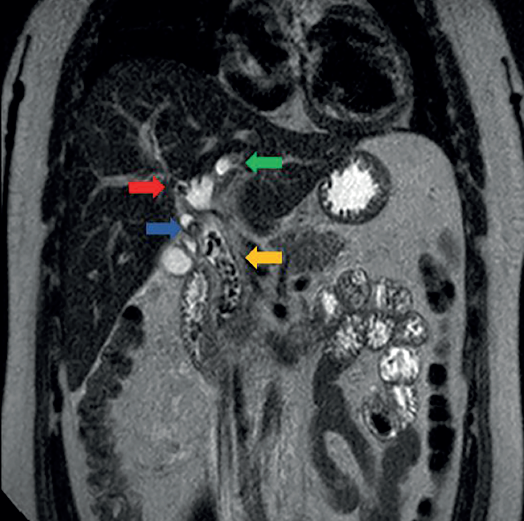

Paciente del sexo masculino, de 31 años, sin antecedentes de importancia. Inició su cuadro con cólico vesicular e irradiación hacia el epigastrio, náuseas, vómito, diaforesis y coluria. A la exploración de abdomen presentó dolor a la palpación media y profunda en el hipocondrio derecho y epigastrio. Estudios de laboratorio: bilirrubina total de 7.0 mg/ dl a expensas de la bilirrubina directa de 5.9 mg/ dl. Se realizó colangioresonancia y se confirmó co ledocolitiasis. Se realizó colangiografía retrograda endoscópica (CPRE) terapéutica exitosa (figura 1).

Figura 1 Colangioresonancia en secuencia T2 en corte coronal en donde se identifican multiples imágenes co ausencia de señal e relación con litos y dilatación de vía biliar intra y extra hepática, conducto hepático derecho (flecha roja) conducto hepático izquierdo izquierdo (flecha verde), conducto cístico (flecha azul), conducto colédoco (flecha amarilla)